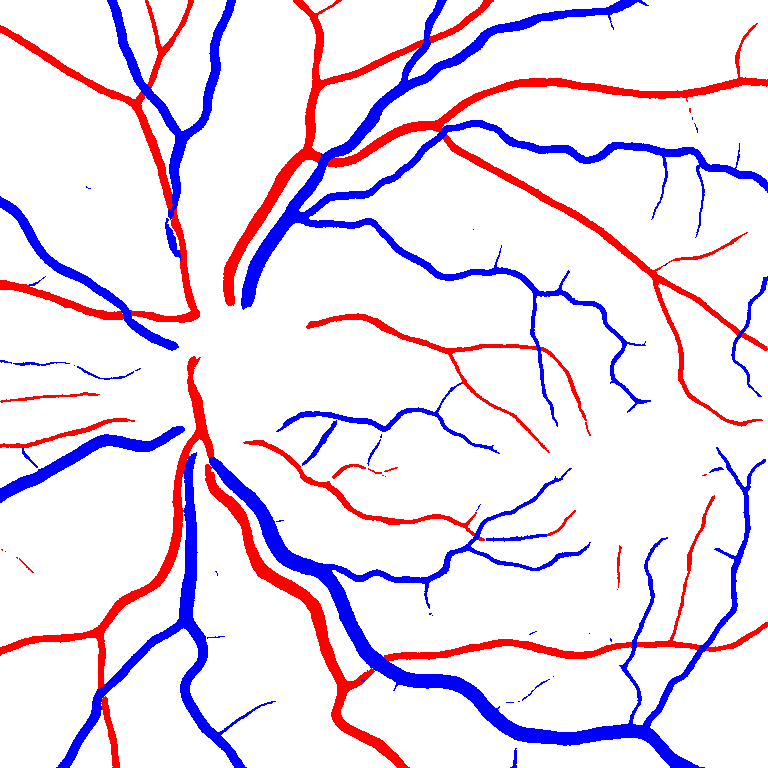

As reported in Table IV, we compared the SegRAVIR model against competing deep learning-based segmentation approaches on the RAVIR dataset. Evidently, SegRAVIR outperforms these methods as judged by all metrics for artery and vein classes with a healthy margin. In terms of Dice score, SegRAVIR outperforms CE-NET, IterNet and AG-Net by , and for artery segmentation and by , and for vein segmentation, respectively. Fig. 4 presents a qualitative comparison of the semantic segmentation outputs of SegRAVIR, CE-Net, and U-Net. Specifically, SegRAVIR yields more accurate vessel topology (i.e., thickness and orientation) segmentation with higher pixel-wise classification accuracy.

Table V presents quantitative performance benchmarks of SegRAVIR and other competing approaches for retinal artery and vein classification on the RITE dataset [11]. SegRAVIR outperforms previous state-of-the-art approaches in terms of accuracy, sensitivity, and specificity. Fig. 5 provides a qualitative comparison between segmentation outputs of SegRAVIR and the method of Hemelings et al. [40] on the RITE test set.